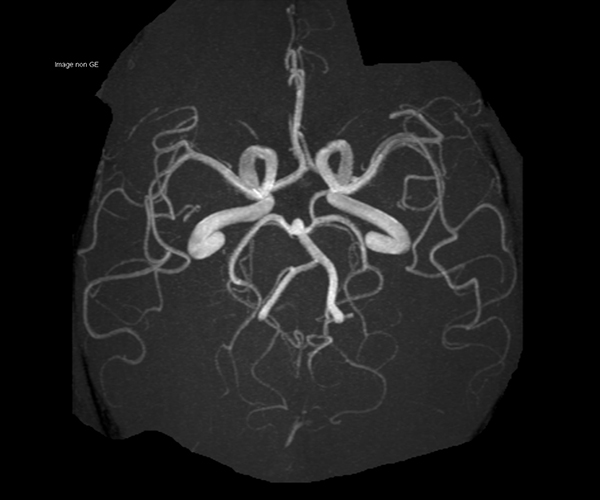

L’augmentation de l’effet de susceptibilité magnétique à plus haut champ permet d’améliorer la détection des hémorragies et est utilisé également dans l’imagerie de perfusion (tumeurs) et l’IRM fonctionnelle (BOLD). L’allongement du T1 à plus haut champ entraîne une meilleure saturation des tissus statiques et par conséquent une augmentation du contraste sang/tissus dans l’AngioIRM.